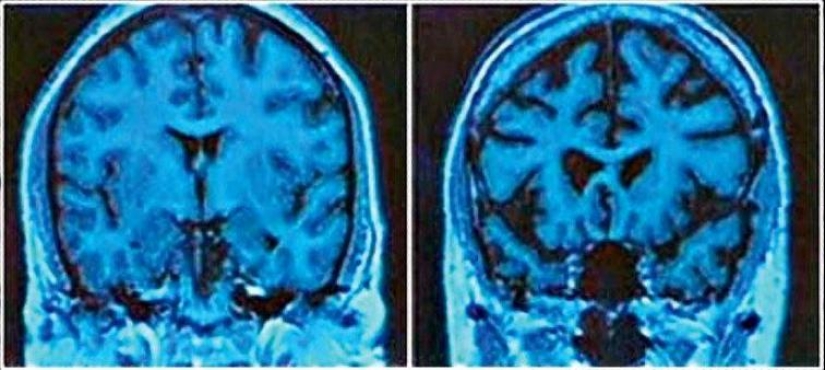

A la izquierda está el cerebro normal de un hombre de 43 años, a la derecha está el cerebro de un alcohólico de 43 años